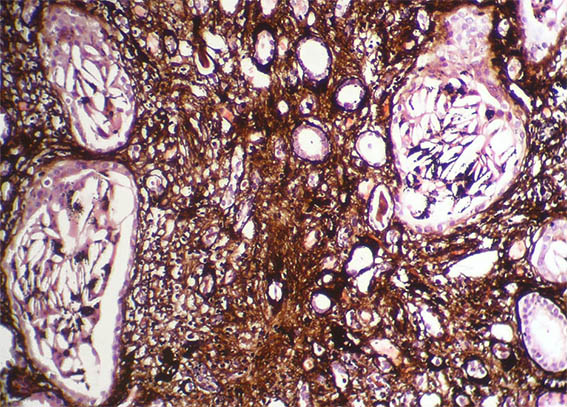

Figure 11. Methenamine-silver stain, X400.